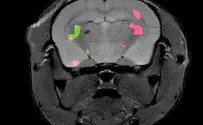

Researchers at the Weizmann Institute of Science have demonstrated how an emerging magnetic resonance imaging (MRI) approach could make pancreatic tumors 'light up' in MRI scans.